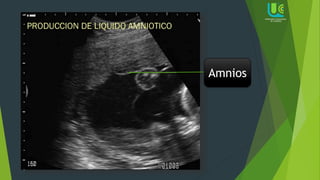

Amnios